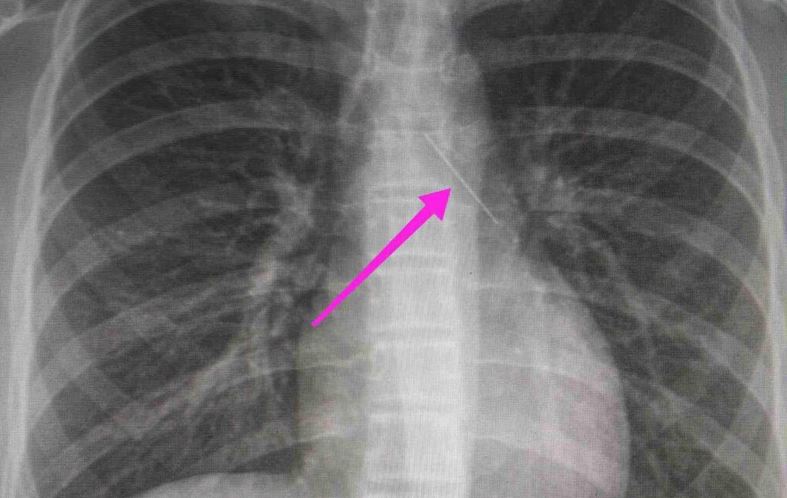

Από την απεικονιστική διερεύνηση που πραγματοποιήθηκε με ακτινογραφία θώρακος αρχικά και ακολούθως με αξονική τομογραφία θώρακος, διαπιστώθηκε η ύπαρξη αιχμηρού μεταλλικού ξένου σώματος στην αναπνευστική οδό (αριστερός κύριος βρόγχος) και όχι στην πεπτική οδό.

Το κορίτσι μεταφέρθηκε αμέσως στο νοσοκομείο και οι γιατροί εντόπισαν αρχικά την καρφίτσα στον αριστερό βρόγχο, στον αυλό που οδηγεί στον πνεύμονα. Όταν όμως έγινε η βρογχοσκόπηση, βρέθηκε στον άλλον βρόγχο.